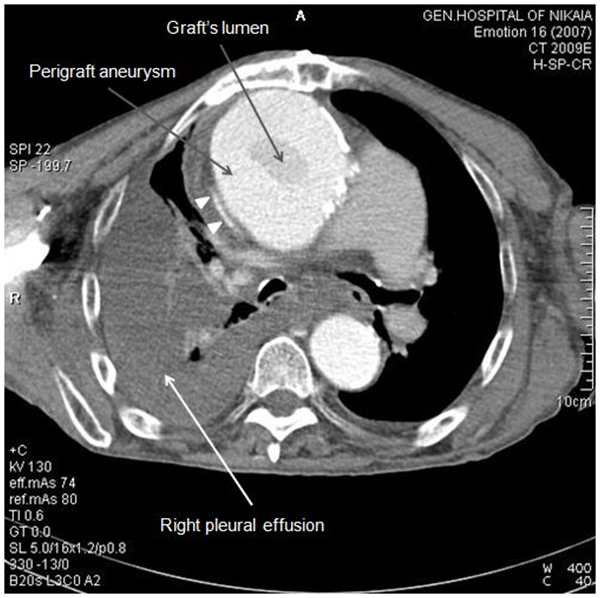

Due to patient’s history, a CT-angiography was immediately performed, which showed a massive perigraft aneurysm, 9x9.5 cm in maximum diameter, extended to the arch, compressing superior vena cava (SVC), brachiocephalic artery, right coronary artery (RCA), and graft partially detached from distal anastomosis, but within the aneurysmal sac Figure (2-7). The aneurysm was probably formed by a leakage at distal anastomosis, between the graft and the native aortic wall which was wrapped around it. A large right pleural effusion was also obvious. However, active leakage of the contrast agent from aneurysmal sac to the surrounding tissues was not observed at that point.

Figure 2 CT-angiography revealed a massive perigraft aneurysm, 9x9.5 cm. Superior vena cava compression (white arrowheads) and right pleural effusion are also manifested.